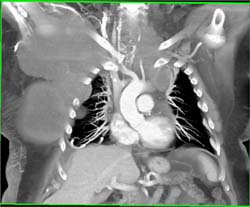

Type A Dissection